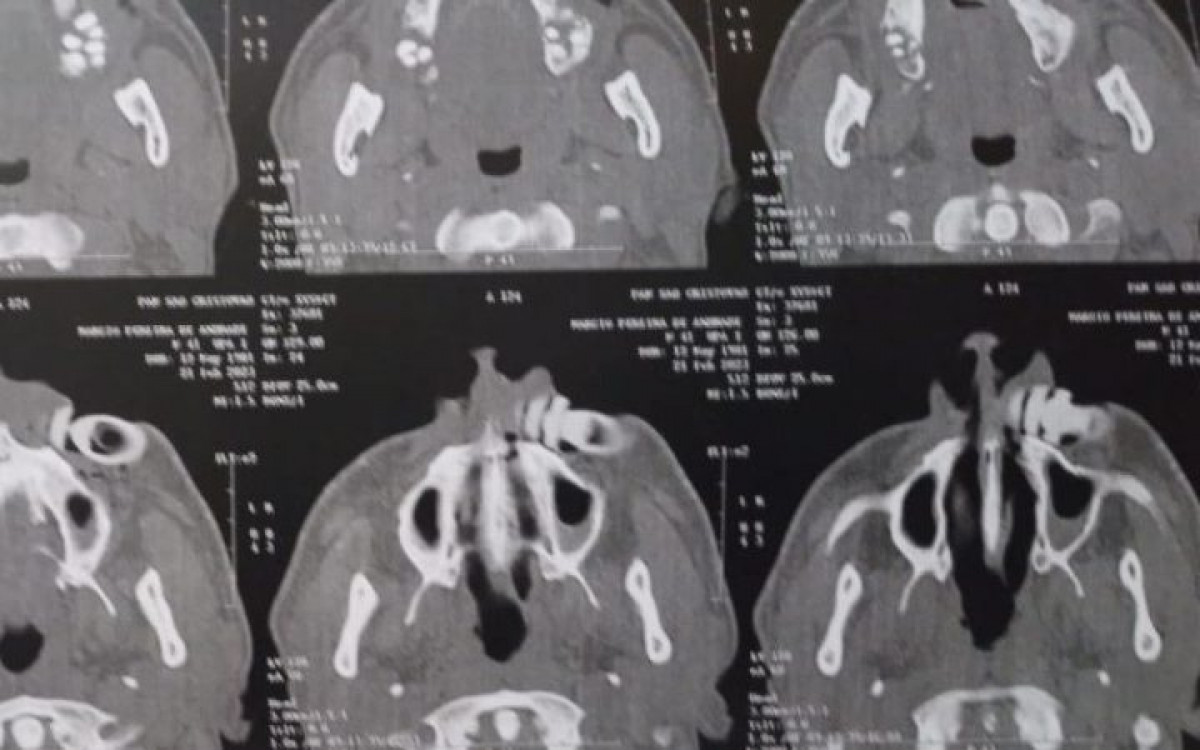

Exame de imagem mostra projetil alojado – Foto: Arquivo pessoal

Logo em seguida, ele foi encaminhado para o Hospital Central de Emergência (HCE), onde realizou exames de imagens, como radiografia e tomografia, sendo constatada a necessidade de uma cirurgia para a retirada do projetil.

Exames solicitados para cirurgia – Foto: Arquivo pessoal

Márcio conta que ainda terá que passar por novos exames e precisará ser submetido a outra cirurgia, dessa vez em um hospital no Rio de Janeiro, já que teve parte do maxilar quebrado e precisará colocar uma prótese. “Não consigo comer, estou tomando água, sopa, tudo com canudinho. Minha boca foi costurada por dentro e por fora”.